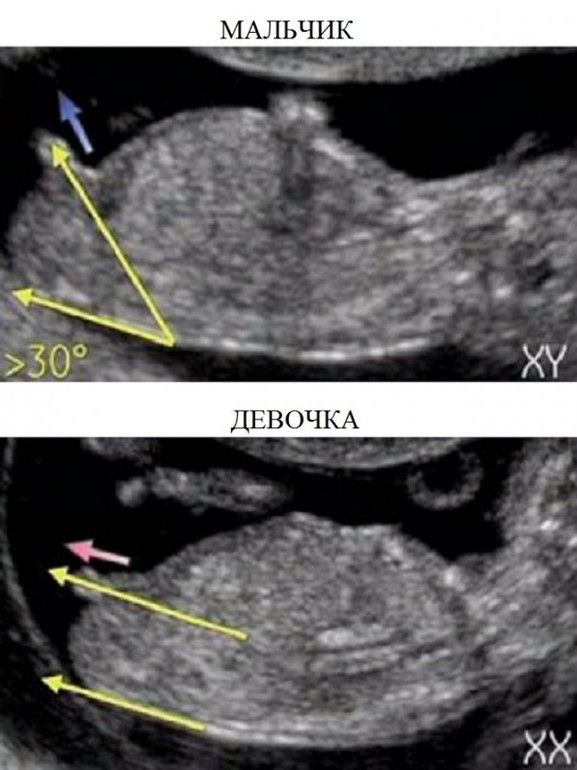

на таком сроке там только половой бугорок примерно одинаковый у мальчиков и девочек) тут за ножкой не особо его видно, оно определяется по направлению бугорочка... через 2-3 недели уже увидят хорошо)